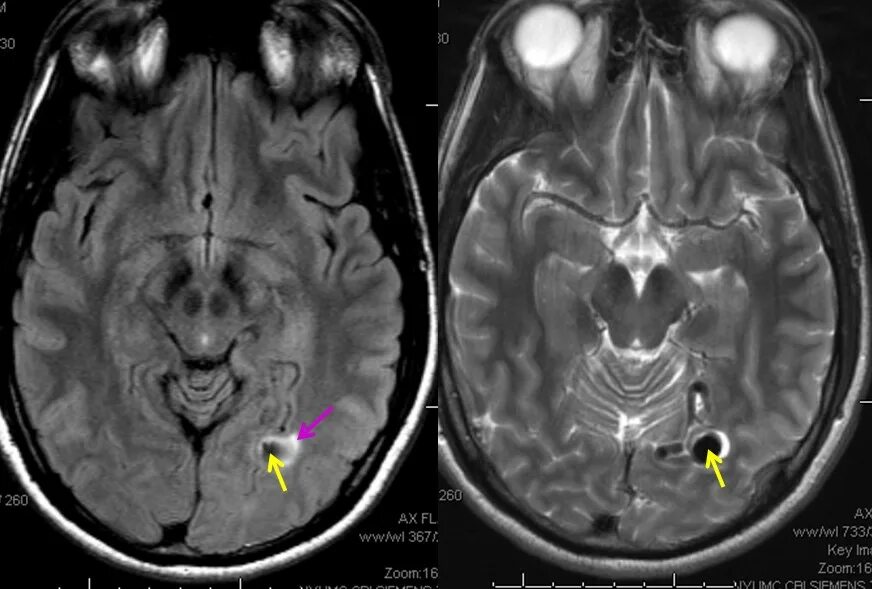

Что можно увидеть на мрт